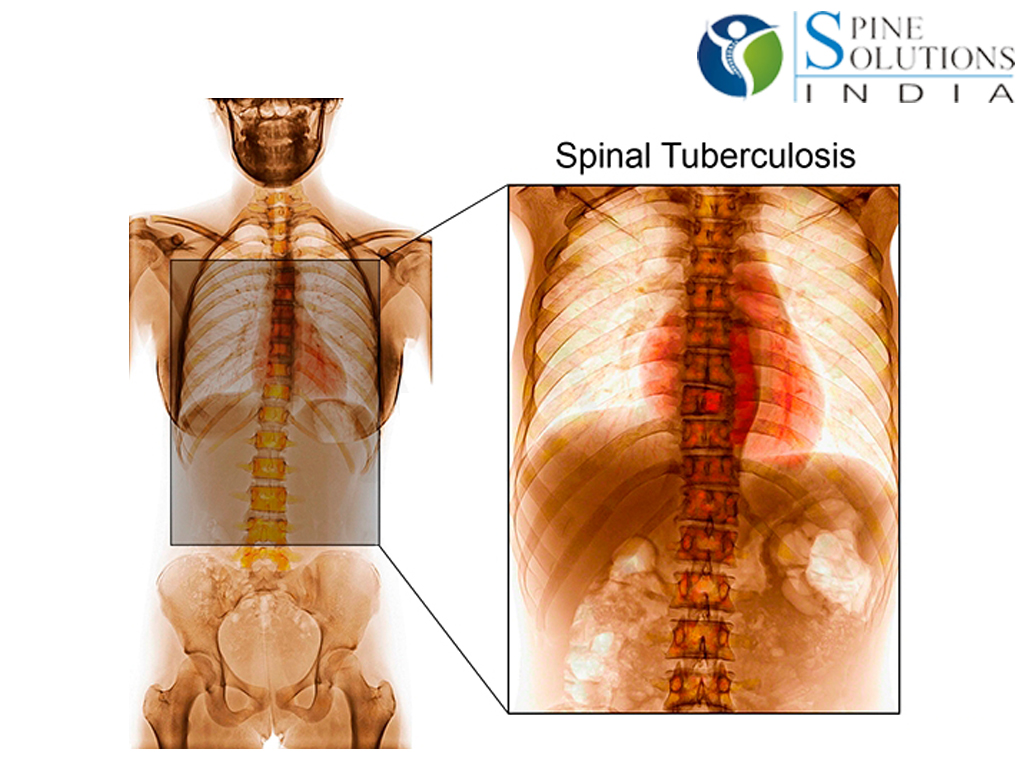

Симптомы туберкулеза: Как распознать и что делать

Раздел: Визуальные уроки